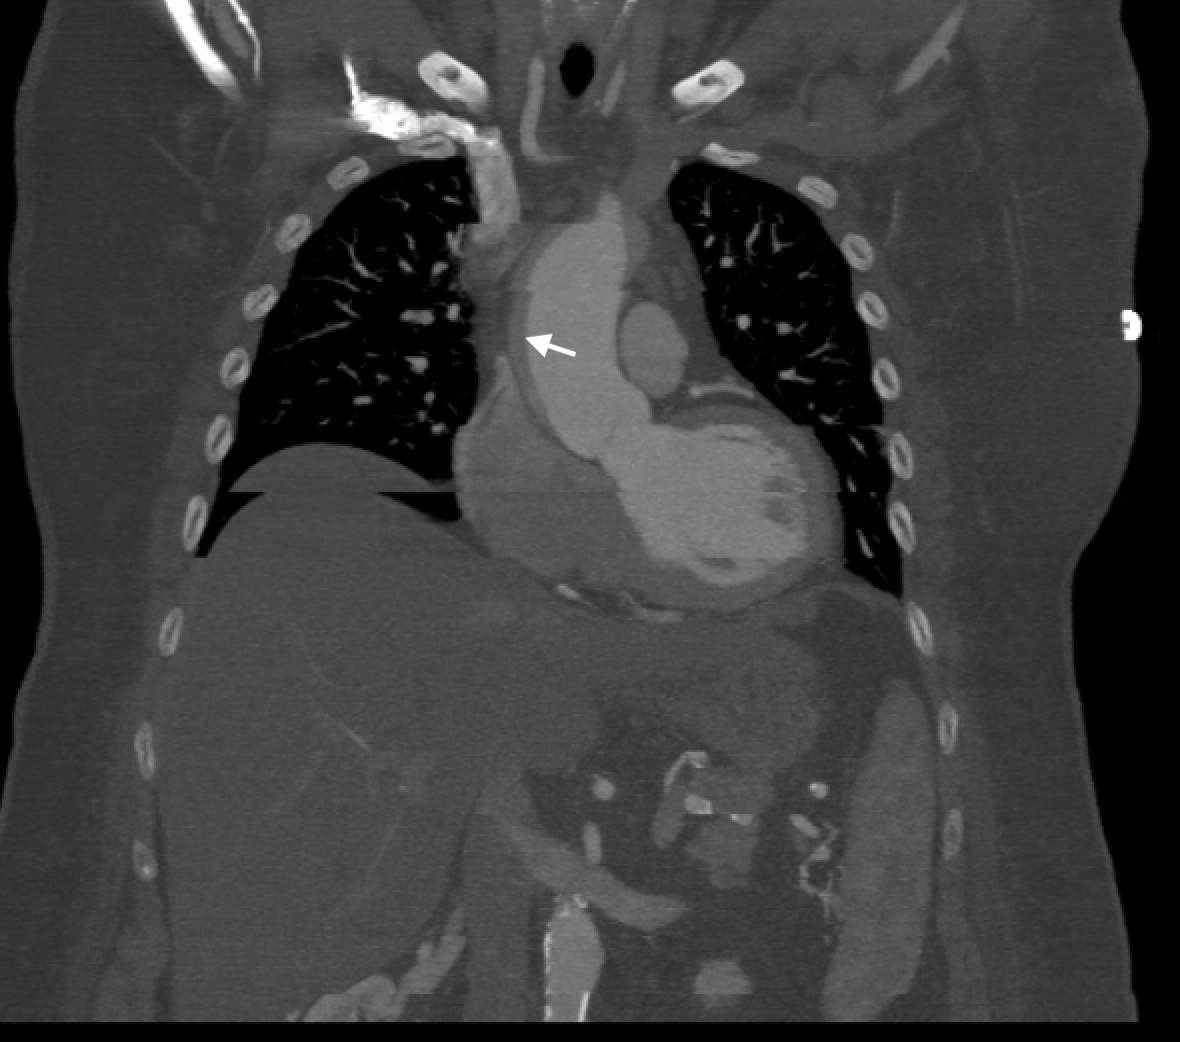

Clinical Case: A 66-year-old female with, history of paroxysmal atrial fibrillation on apixaban and DVT, presented to the emergency department due to epigastric discomfort. Ischemic evaluation was negative. Two weeks later patient had a follow up visit and reported ongoing symptoms. Coronary CT angiography was completed and showed 70-75% stenoses of Left Main and Left Anterior Descending arteries. The patient underwent coronary angiogram, confirming the diagnosis. During guide catheter introduction for IFR measurement, the artery was dissected and the dissection flap extended retrograde to the aortic root and ascending aorta. Prompt placement of a drug eluting stent in the left main was performed. Post-dilation, the dissection flap had closed. Patient was started on IV cangrelor, high dose beta blocker and transferred to the cardiac ICU. CTA chest demonstrated dissection flap in ascending and descending aorta. Cardiothoracic surgery was consulted and opted to observe with follow up imaging as patient was hemodynamically stable. Follow up CT chest showed a stable dissection flap, IV cangrelor was switched to aspirin and clopidogrel, and home apixaban was resumed. Hospital course was uneventful except for an episode of atrial fibrillation with rapid ventricular response, treated accordingly with beta blocker and amiodarone. CT chest in one month demonstrated an increase in aortic intramural thickness from 3.3mm to 9mm. Aspirin and apixaban were discontinued and retrievable IVC filter was placed. CT chest one month later demonstrated complete resolution of ascending intra-mural hematoma. Patient’s apixaban was resumed. CT chest in two weeks showed no new hematoma. IVC filter was removed and patient remained asymptomatic during the follow up course. Given patient had family history of aortic aneurysm and dissection, genetic testing was pursued and was negative.